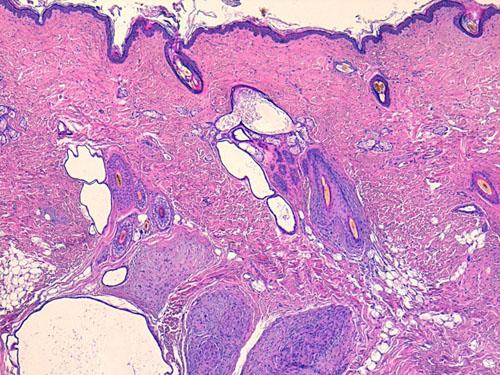

Les nouvelles biopsies mettent en évidence dans le derme profond et l’hypoderme des images identiques de lésions multi-nodulaires, non encapsulées, au sein d’une prolifération cellulaire diffuse de cellules fusiformes. Ces cellules sont peu nombreuses, sans atypie cyto-nucléaire, organisées en faisceaux dans les tissus environnants et les structures annexielles. Ces lésions sont traversées par de nombreuses structures nerveuses périphériques normales. L’épiderme est hyperpigmenté en regard des zones nodulaires (photos 6 à 8).

Photo 6 (HE*40, LAPVSO) : lésions multinodulaires dans le derme profond